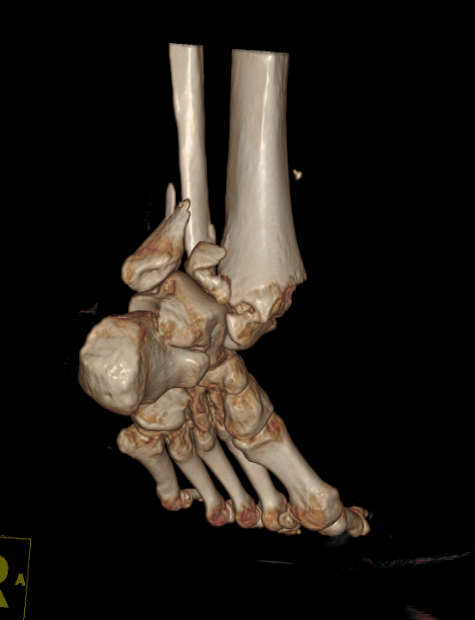

病例五:患者,女,56岁,因“车祸伤致左踝关节肿痛伴活动受限14小时”入院。诊断:左侧三踝粉碎性骨折伴踝关节脱位;行左踝关节骨折切开复位内固定术;手术顺利,术后进行康复训练中,功能恢复良好。

左侧三踝粉碎性骨折 术前三维CT